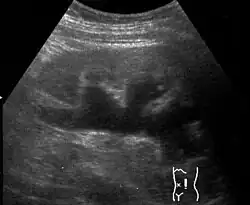

| Renal ultrasonography of hydronephrosis caused by a left ureteral stone | |

Renal ultrasonography of hydronephrosis[16]